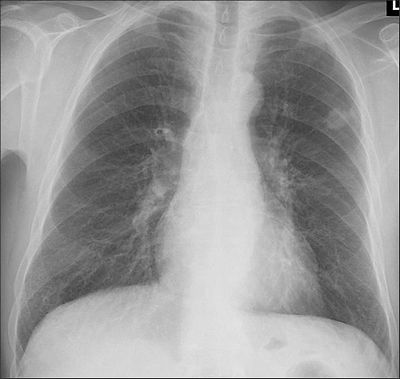

Röntgenbild einer Lunge

(Foto: de.wikipedia.org)

Nach dem letzten Krieg tauchte in Altrip verstärkt eine weitere Infektionskrankheit auf: die Lungentuberkulose. Vielleicht war dies mit ein Grund dafür, dass Altrip als Pilotprojekt für ein transportables Röntgengerät ausgewählt wurde. Ende Juli 1951 erhielt Bürgermeister Adam Jacob die Mitteilung, dass schon im August das Modellvorhaben gestartet werde. Diese „Schirmbild-Aktion“ war ein völlig neues Verfahren für eine kostengünstige Röntgen-Reihenuntersuchung des Thorax.

Auf einem Lastwagen wurde das Gerät nach Altrip befördert, wo seine Einzelteile von Technikern in einer Dreiviertelstunde zusammengebaut wurden. Ziel war die Erfassung der potenziell betroffenen Bevölkerung. Von der Technik her war es eine „normale“ Durchleuchtung, bei der der Patient zwischen der Röntgenröhre und dem Schirm stand.

Nachdem der Arzt der Tbc mit „Horchgeräten“ nicht auf die Spur kommen konnte („Tuberkulose wird nicht gehört; sie ist nur zu sehen!“), entwickelten amerikanische und deutsche Forscher entsprechende Röntgenapparate, die nach dem Krieg vervollkommnet wurden. Als erste Städte in der Pfalz schafften sich Kaiserslautern und Ludwigshafen solche Röntgengeräte an. Neben Schulkindern, Lehrern und Angehörigen Tbc-gefährdeter Berufe wurden im Gesundheitsamt Ludwigshafen auch allwöchentlich die Eheanwärter „beäugt“, insbesondere solche, die familiär vorbelastet waren.

Die heute 78-jährige Erna Wüst erinnert sich noch genau, dass sie damals als Kanzleiangestellte für das Standesamt stets Anfragen beim Gesundheitsamt starten musste. Mit dem in Altrip eingesetzten Schirmbildgerät wurden binnen weniger Tage über 1370 Männer und Frauen erfasst. Die Auswertung selbst erfolgte anschließend im Gesundheitsamt. Die staatliche Tuberkulosefürsorge war mit dem Gesamtergebnis „sehr zufrieden“.